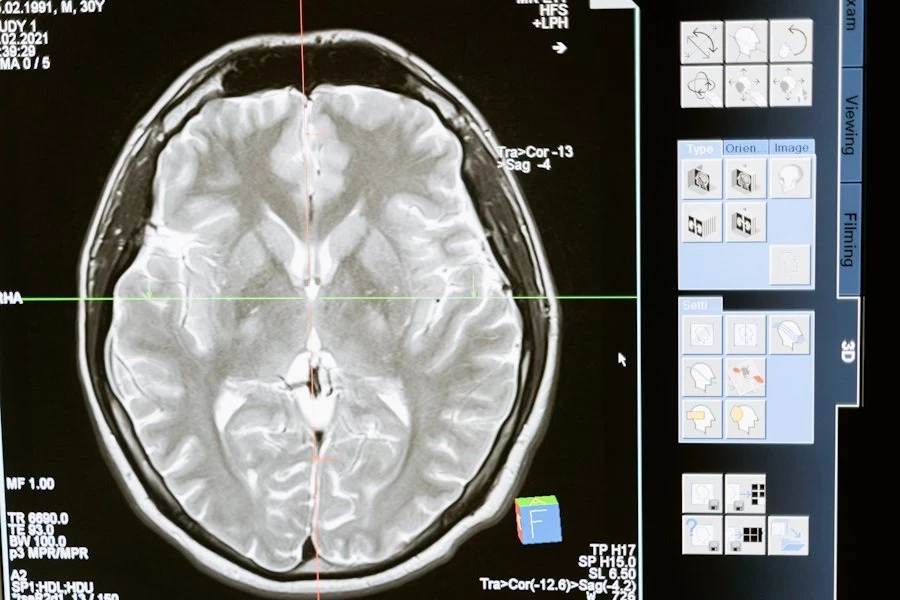

Учеными из University of Texas at San Antonio разработан инструмент на основе искусственного интеллекта, выявляющий нарушения в мозге по снимкам МРТ буквально за несколько секунд. В конечном итоге это позволит специалистам диагностировать заболевания головного мозга на более ранних стадиях. Результаты работы опубликованы в журнале JAMA Network Open.

Как это работает: инструмент обращает внимание на особые области в мозге, которые окружены жидкостью и связаны с кровеносными сосудами. Эти места могут показать проблемы с мелкими сосудами мозга, которые могут привести к серьезным болезням, таким как инсульт или деменция.

Инструмент был проверен на данных 1026 человек, и он смог точно определить количество и местоположение этих особых областей в мозге. Ранее такие области были очень сложно и долго считать вручную на снимках МРТ — на одном снимке могло быть до 600 таких областей, и у врача на это уходило много времени. Теперь же благодаря этому инструменту все делается автоматически и очень быстро.